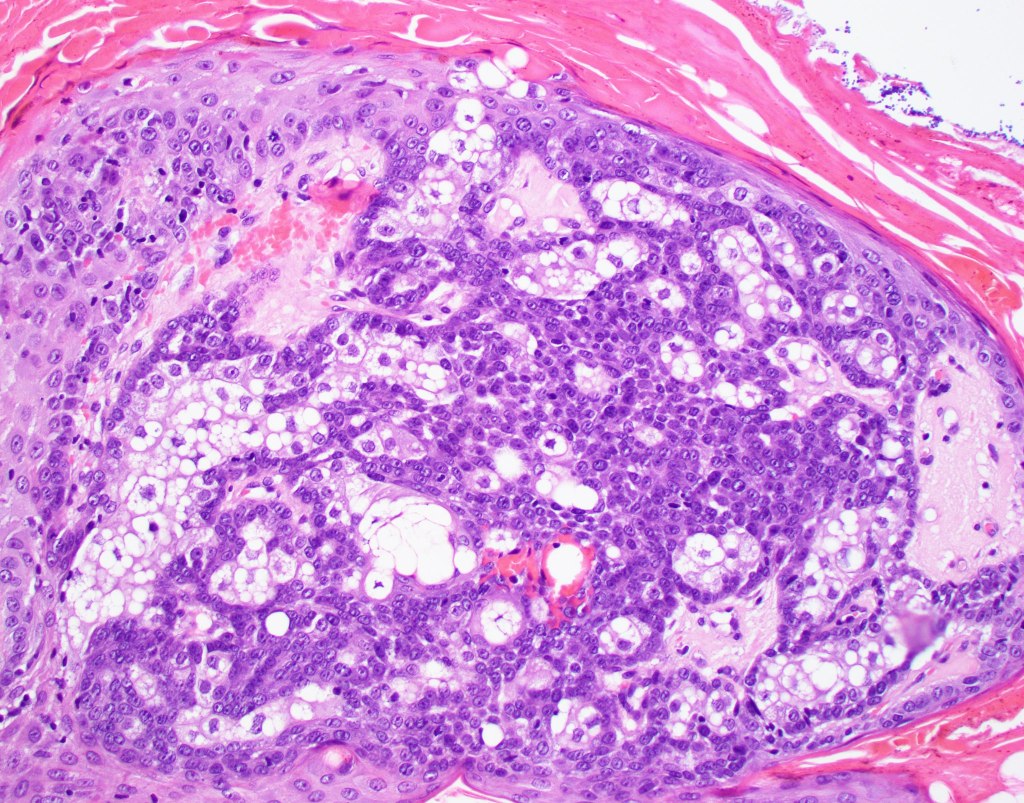

Histological features

•Variable origin from epidermis

•Typically multilobulated, occasioanlly cystic

•Collagenous pseudocapsule

•At the periphery, single or multiple germinative cell layers maturing into typical sebaceous cells (>50%)

•Variable peripheral palisading

•+/- basal mitoses (particularly in the so-called giant variant which should not be misdiagnosed as sebaceous carcinoma)